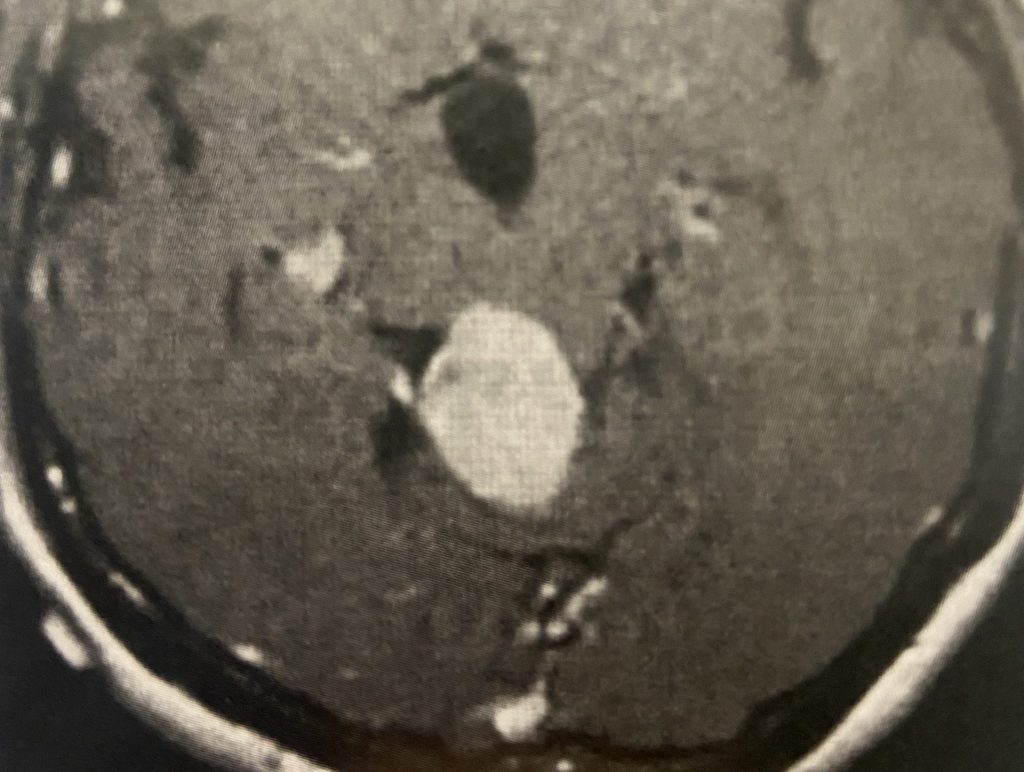

MRI with gadolinium confirmed the likely diagnosis of convexity meningioma, a benign neoplasm of the meninges. Given the location of the tumor, angiography and embolization were […]